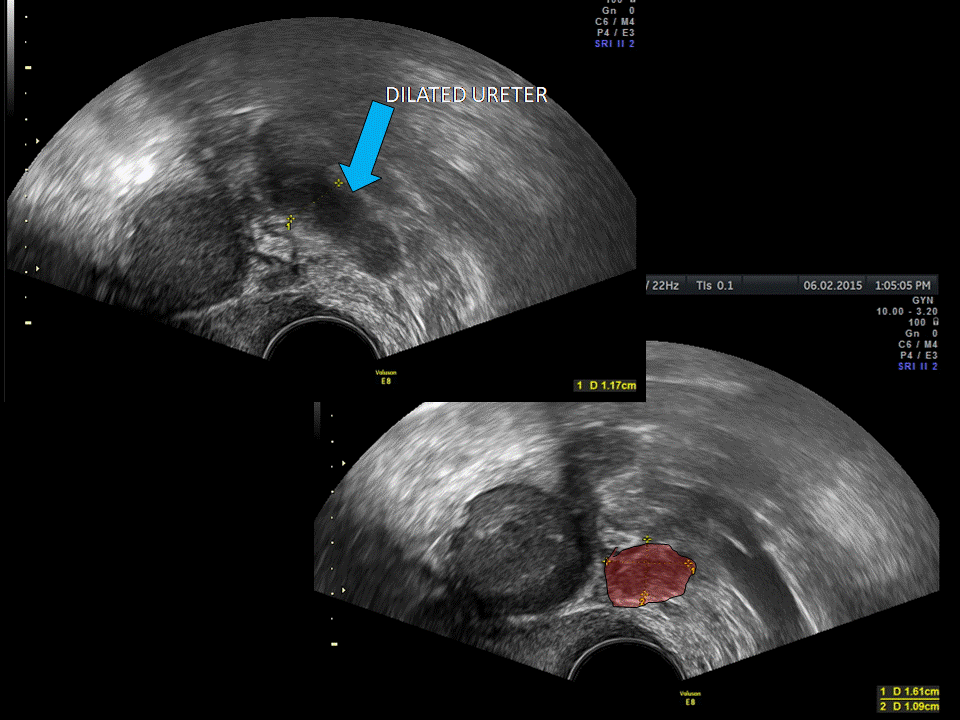

From www.volusonclub.net

Using Transvaginal Ultrasound for Ureteral Endometriosis Empowered Pelvic Exam Endometriosis About half of women with endometriosis will have a perfectly normal pelvic exam. Endometriosis is defined as endometrial glands and stroma that occur outside the uterine cavity. Can endometriosis be detected by a pelvic exam? Doctors can perform a pelvic exam to check the vagina, cervix, uterus, ovaries, pelvis, rectum, and vulva for gynecologic issues such as. Offer an abdominal. Pelvic Exam Endometriosis.